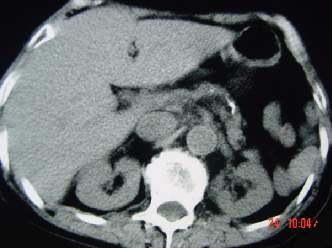

问题 女,54岁,中上腹痛,体重减轻,消化不良,脂肪痢、便量多、泡沫状。影像检查如下图,最佳诊断是 ( )

选项 A、急性出血坏死性胰腺炎 B、胰岛素瘤 C、慢性胰腺炎 D、胰腺癌 E、急性胰腺炎

答案 C